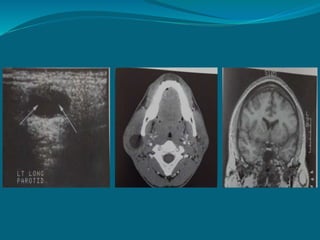

Ultrasound

 High resolution scanners produce excellent images.

Indications:

 Discrete & generalised swelling both intrinsic and

extrinsic to gland.

 Salivary obstruction.

 Differentiate solid masses from cystic ones.

 Guided fine needle aspiration biopsy.

*

Benign tumour Sialolith

MRI

 Provides superior soft tissue contrast resolution than

CT.

 Fewer problems with streak artifacts from metallic

dental restoration.

 Image – multiplanar reconstruction software

algorithm.

 iv contrast(gadolinium) – Differentiate cystic & solid

masses.

MRI revealing lymphoepithelial

cyst involving right parotid